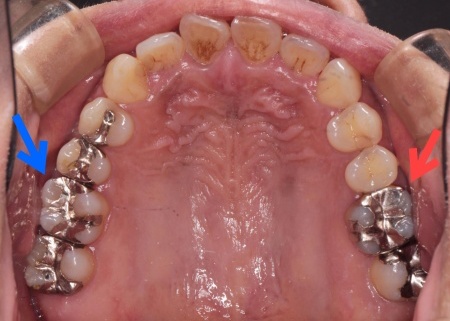

| 診断 | 患者様には、まず皮膚科での金属アレルギー検査をおすすめしたところ、歯科治療で使用していた金属がアレルギーの原因と判明しました。 患者様の口腔内には、金属素材で修復が行われている部位があり、これが体調不良につながっていたと考えられます。 以上のことから、口腔内の金属をすべて除去し、金属を使わない材料で修復する必要があると診断しました。 |

| 行ったご提案・治療内容 | 患者様は噛む力が非常に強く、その影響でエナメル質が割れてしまっています。 そこで詰め物の素材には、自費診療の白い素材「セラミック」の中でも、人工ダイヤモンドと呼ばれるほど強度があり、審美性にも優れている「ジルコニア」を選択しました。 すべての詰め物にジルコニアを用いるのが理想でしたが、ジルコニアは費用が高額です。 詰め物の形状には、歯の溝や一部を補う小さな詰め物「インレー」と、歯の噛む面を広範囲で覆う「アンレー」があります。 まずはメタルインレーをすべて外し、詰め物を装着するために歯の形を整え、型取りを行います。 |

治療前